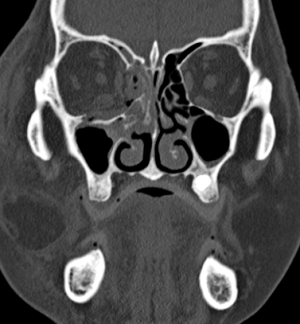

Computerized tomography is the imaging of choice for evaluating suspected orbital and orbitofacial fractures, intraorbital and intraocular foreign bodies and traumatic optic neuropathies. In the trauma setting, it is generally performed as a non-contrast study, with contrast indicated only in cases where there is concern for carotid-cavernous fistula. Axial images are useful in evaluation of the medial and lateral orbital walls, in addition to the medial and lateral rectus muscles. Coronal images are similarly useful in scrutinizing the superior and inferior orbital walls, the superior and inferior rectus muscles, and identifying optic nerve sheath hematoma. [29] While soft tissue window is useful for gross disruptions of the bone and soft tissue changes (EOM, Fat, Optic nerve, Brain, etc), Bone Windows are much more sensitive to detect orbital and orbitofacial fractures and should be viewed in the axial, coronal and sagittal views.

In the setting of orbital wall fracture, CT scan can often be helpful in demonstrating entrapped extraocular muscles. CT typically demonstrates linear floor fractures with minimal displacement and little or no soft tissue displacement in the maxillary antrum. However, associated soft tissue swelling, fat stranding, and muscular hematoma can often make radiographic interpretation difficult, especially in children where CT findings of entrapped extraocular tissues can be minimal. This emphasizes the importance of clinical exam using assessment of extraocular motility and forced ductions. Finally, CT can also be used o estimate the fracture area, which can be utilized as criterion for operative repair. [30]

In situations where a detailed clinical examination is not possible and there is a high suspicion of globe disruption, a CT scan may be indicated.[31] In patients with a clinical diagnosis of traumatic optic neuropathy, CT can be employed to asses for optic nerve canal fracture, foreign body, or bony impingment on the nerve.[32] It can also be employed for intraoperative navigation of the orbitofacial skeleton with 3-D modeling, in which images are acquired in the 0.6 – 1 mm formats. 3D reconstructions may be performed for patient education and treatment planning, which may be used for prebending orbital implants.

CT can also aid in the diagnosis of “open globe” injuries, defined as a full-thickness disruption of the sclera or cornea of the eye. Findings suggestive of an open globe injury on CT include a disruption of the globe contour, change in globe volume, variation in anterior chamber depth, and finally intraocular air, blood or foreign body. In one study, the sensitivity and specificity of detecting open globe injuries with CT was estimated at 75% and 93%, respectively. Therefore, although useful in the evaluation of traumatic injury to the globe, CT should not be relied upon solely for the assessment of open globe injuries. [29] Finally, CT scans of the orbits and face and not infrequently to assess completeness and accuracy of orbital reconstruction following fracture repairs, especially when postoperative complicaitons such as strabismus, motility disorders or optic neuropathy.